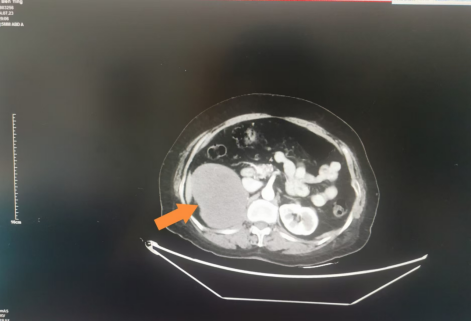

家住六安市裕安区的徐老太今年74岁,最近在当地医院行胸部CT检查时无意中发现右侧腹膜后巨大占位性病变。家人赶忙带着徐老太来到市中医院泌尿外科就诊。经过系列检查,医生发现徐老太的肝肾间隙长有一枚巨大占位性病变,大小约14*9cm,包绕部分肾动脉,考虑来源于腹膜后组织。

经过与患者家属沟通,完善各项术前准备后,泌尿外科李磊团队为徐老太实施了腹腔镜下右侧腹膜后肿瘤切除术。手术顺利,术中出血30ml,测量肿瘤大小约14*9*8cm,术后患者恢复良好。